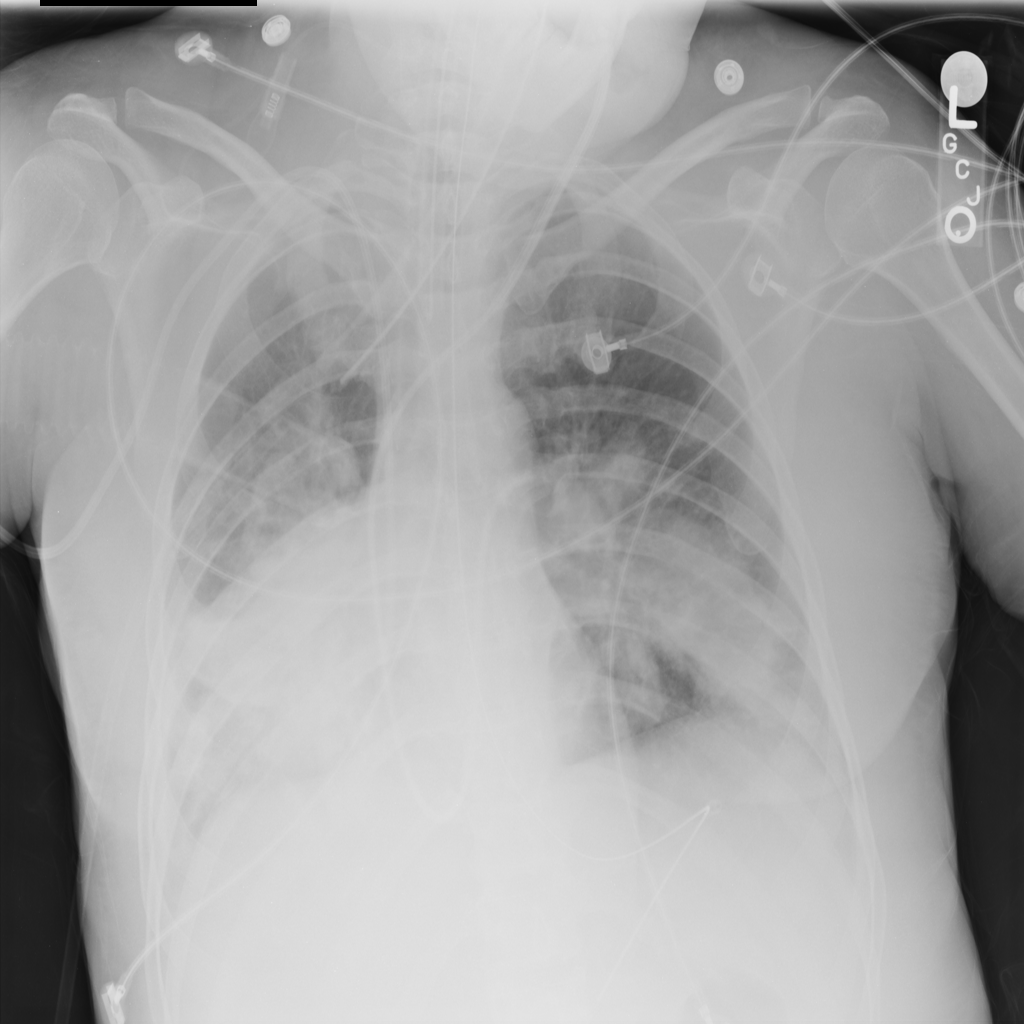

PAT-64EB · IMG-015Consolidation

PAT-64EB · IMG-015

AP